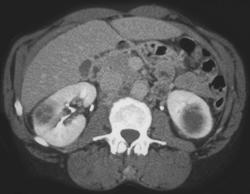

Hypervascular Renal Cell Cancer in Right Kidney